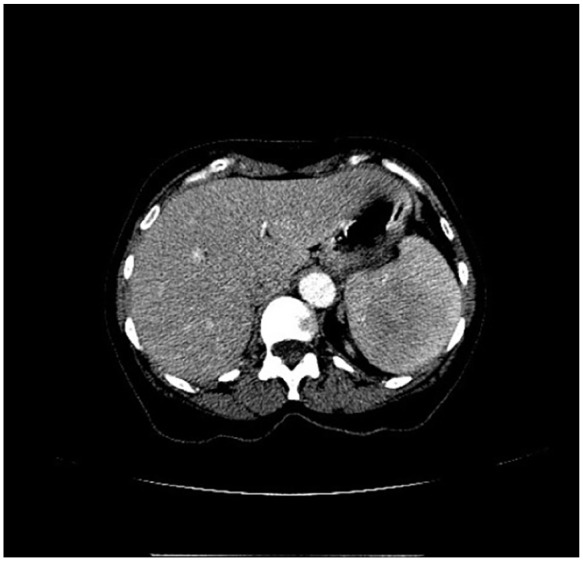

Littoral cell angioma (LCA) is a rare primary splenic vascular neoplasm originating from the littoral cells of the reticuloendothelial system. Splenectomy is the accepted mode of definitive diagnosis and treatment. With fewer than 200 reported cases, LCA remains poorly understood. Herein, we provide an enhanced insight into its histology and highlight the role of nuclear imaging in aiding LCA diagnosis. A 63-year-old female with a history of stage II multiple myeloma (MM) and rheumatoid arthritis was incidentally found to have a slowly enlarging splenic mass over a 6-year period. Given her candidacy for autologous hematopoietic stem cell transplantation for MM, further evaluation of the splenic lesion was pursued using nuclear medicine (NM) liver-spleen scan, which revealed a photopenic region consistent with a benign hemorrhagic mass. Subsequent splenectomy and histopathological analysis confirmed the diagnosis of LCA, with immunohistochemistry demonstrating CD68+ and CD31+ expression, highlighting LCA's unique dual histiocytic and endothelial character. This case highlights the diagnostic challenge posed by LCA due to its nonspecific clinical presentation and imaging findings. While splenectomy remains the gold standard for diagnosis, our findings suggest that NM liver-spleen scan imaging may aid in differentiating LCA from malignant splenic masses preoperatively. Furthermore, this case reinforces the association between LCA and hematologic malignancies, supporting the hypothesis that immune dysregulation may play a role in its pathogenesis. This underscores the importance of considering LCA in the differential diagnosis of splenic masses, particularly in cases involving a history of malignancy and/or immune system abnormalities.